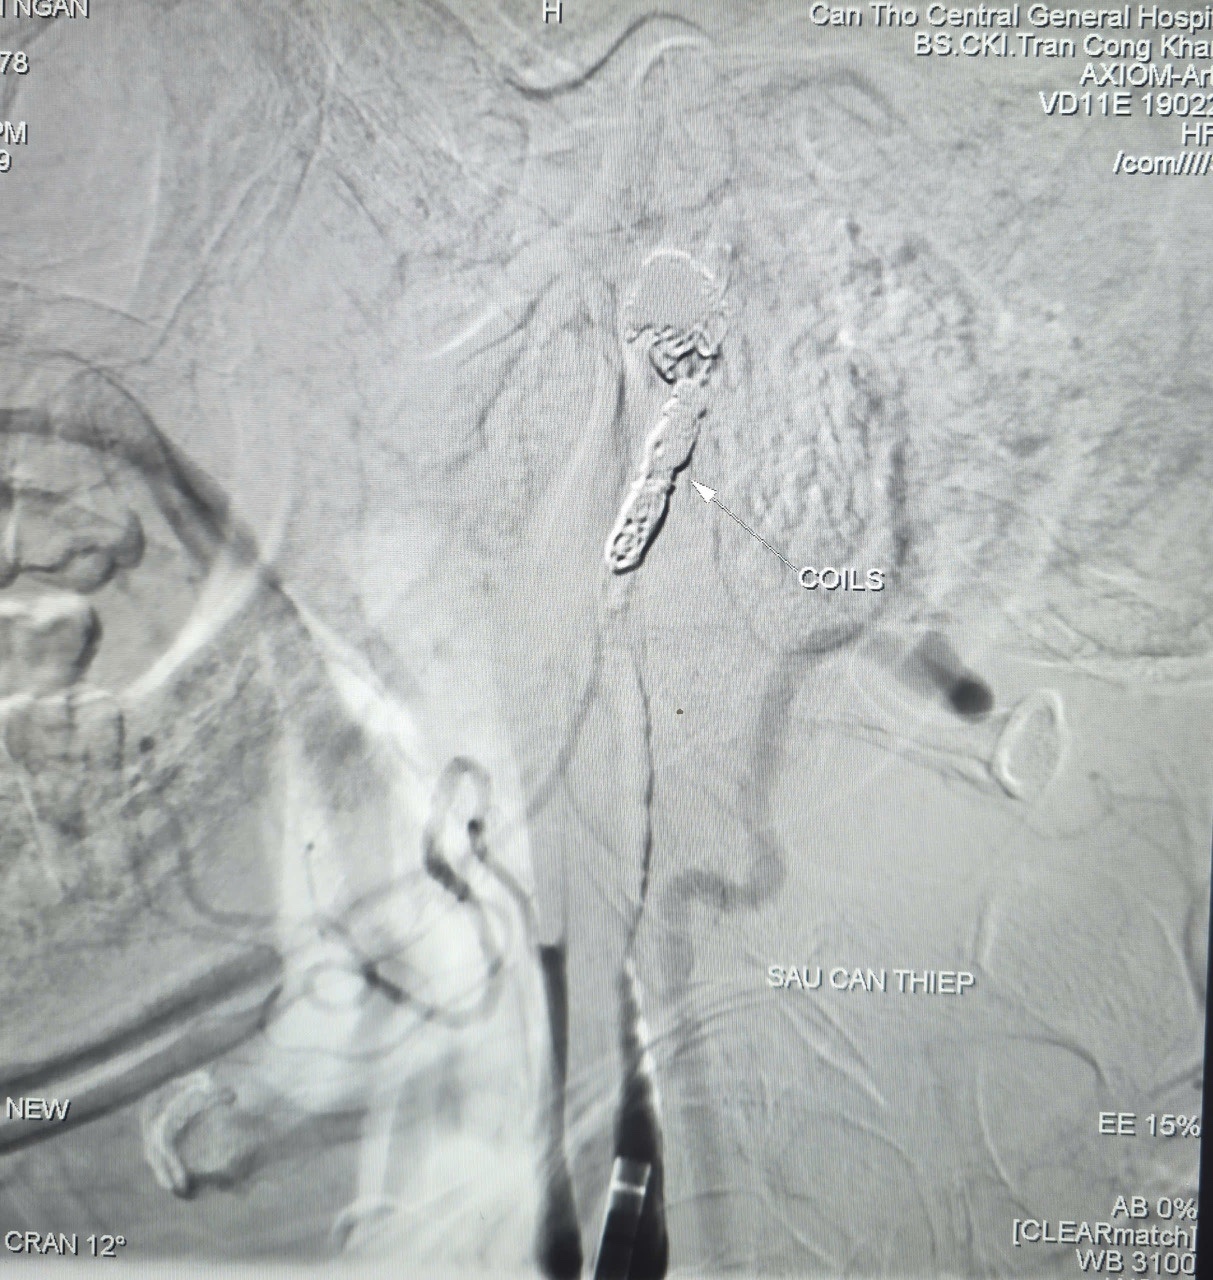

Kết quả chụp mạch ghi nhận ổ giả phình động mạch cảnh trong phải đoạn cổ, kích thước 4,2 x 4,8 mm, cổ túi phình rộng và đang chảy máu. Ê-kíp đã sử dụng bóng chẹn dòng chảy, sau đó đưa vi ống thông đến vị trí tổn thương và thả 9 vòng xoắn kim loại (coils) gây tắc hoàn toàn túi phình và động mạch cảnh trong phải nhằm kiểm soát nguồn chảy máu.

Chụp kiểm tra từ động mạch cảnh trong trái cho thấy hệ tuần hoàn bàng hệ vẫn đảm bảo tưới máu cho bán cầu não phải. Toàn bộ thủ thuật được hoàn tất trong 90 phút.